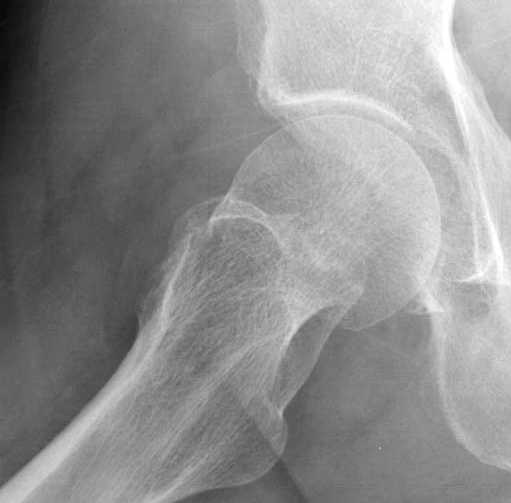

На второй день после выписки упал дома. Снимки приложены. Коллеги рекомендуют удаление шурупа и вытяжение. Что делать?

Привет из солнечного Будапешта с Eurotrauma-2008. Да, замечательный пример. Получается, профилактику расхождения отломков шейки надо было проводить каким-то реконструкционным или проксимальным гвоздем, причем сразу длинной версией. Сейчас, наверно, так и надо бы сделать.

Но ведь и головка бедра сползла в варус - отчего ограничились только фиксацией подвертельного перелома, а не убрали винты и не сделали репозицию шейки?